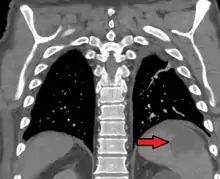

Splenic infarct seen on CT

Splenic infarction is a condition in which blood flow supply to the spleen is compromised,[1] leading to partial or complete infarction (tissue death due to oxygen shortage) in the organ.[2] Splenic infarction occurs when the splenic artery or one of its branches are occluded, for example by a blood clot.[3]

An abdominal CT scan is the most commonly used modality to confirm the diagnosis,[3] although abdominal ultrasound can also contribute.[5][6][7]